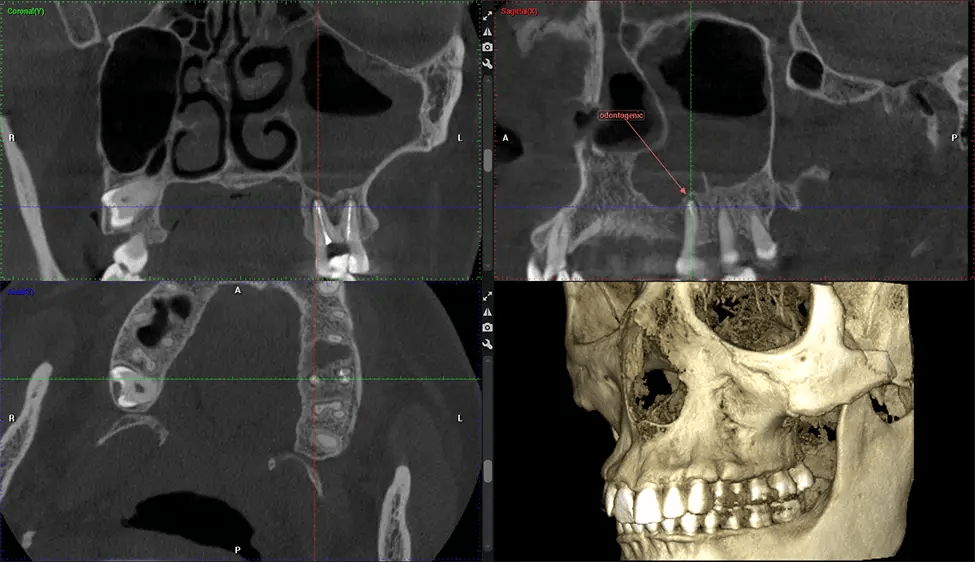

Esta exploración 3D, llamada tomografía computarizada de haz cónico, le brinda a su dentista una imagen más completa de su anatomía bucal y sus procesos patológicos que una radiografía tradicional. A diferencia de las radiografías convencionales, que capturan una imagen 2D de la boca desde varios ángulos, una exploración 3D toma varias radiografías digitales para una imagen. Proporciona una vista completa de la mandíbula, los dientes, los nervios y los tejidos blandos. Esta vista mejorada permite a los dentistas detectar problemas menores que no son visibles en las exploraciones 2D tradicionales, como muelas del juicio impactadas o fracturas óseas en la cavidad sinusal.

Existen muchos beneficios al utilizar la tecnología CBCT, especialmente en comparación con el formato tradicional de rayos X 2D. Una de las ventajas más importantes de las exploraciones CBCT es que proporcionan mucha más información que las radiografías tradicionales. Una exploración le permite a su dentista ver imágenes desde todos los ángulos de su mandíbula y boca, incluidos los senos nasales, la cavidad nasal, los pómulos y otras áreas circundantes. Esta información adicional ayuda a su dentista a elaborar un plan de tratamiento integral que aborde todos los aspectos de su salud bucal.

Otro beneficio importante es que las imágenes 3D proporcionan imágenes más precisas de la estructura ósea. Estas imágenes son más detalladas y le brindan un diagnóstico más preciso. Un diagnóstico preciso significa un mejor tratamiento para usted.